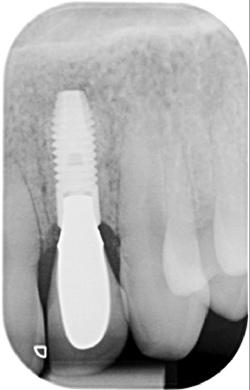

Ein Zahnimplantat ist eine künstliche Zahnwurzel aus Reintitan, die dauerhaft in den Kieferknochen eingesetzt wird. Durch den Prozess der Osseointegration verwächst das Implantat fest mit dem Knochen und bildet eine stabile Basis für Zahnersatz wie Kronen, Brücken oder Prothesen.

Ein vollständiges Implantat besteht aus: